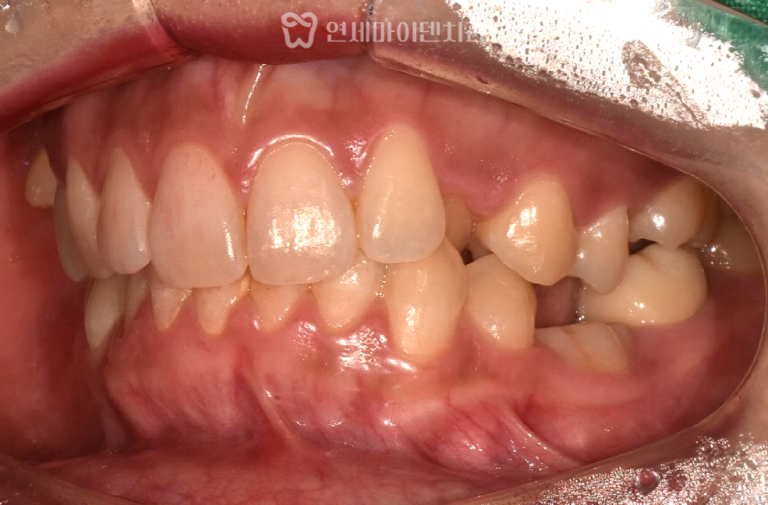

환자분은 과거에 시술받은 임플란트 중

일부 보철물이 파절된 상태였습니다.

하지만 다행히 임플란트 본체는 건강하게 유지되고 있었습니다.

이에 따라 기존 임플란트는 그대로 두고,

상부 보철물만 새로 제작했습니다.

이번에는 교합면 방향과 잇몸 형태를 고려하여

맞춤형 지대주(abutment)를 적용했습니다.

이는 향후 파절 위험을 줄이고

심미적 완성도를 높이는 데 도움이 됩니다.